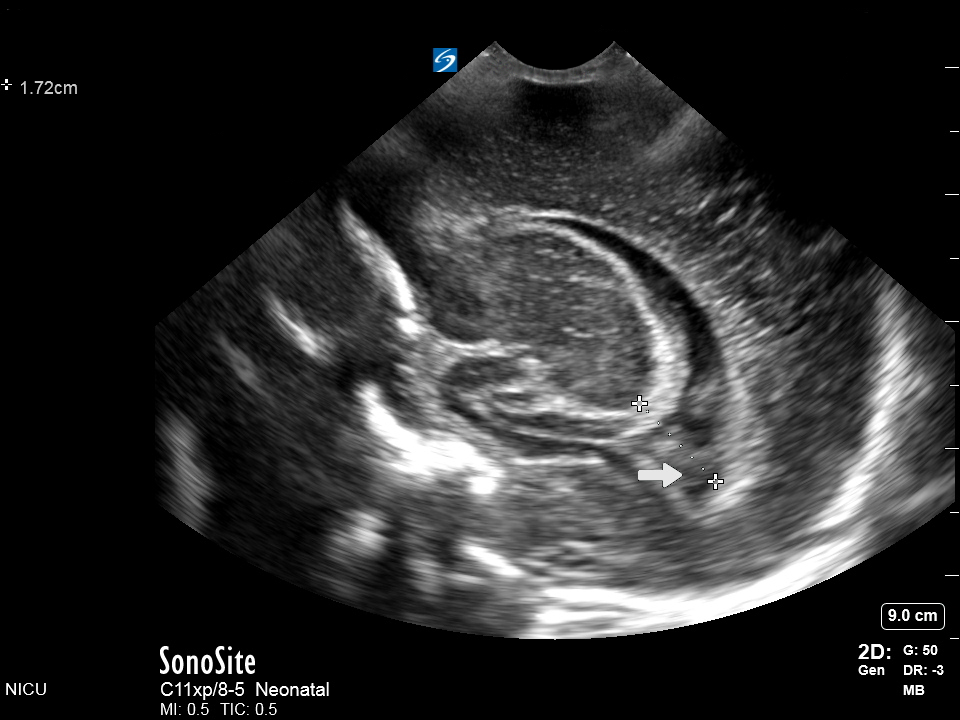

Neonatology Sagittal View Occipital Horn Clot 1 Image